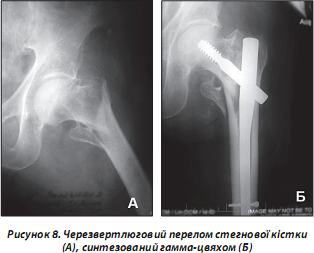

Поява вперше в травматології у 1986 році гамма-цвяха призвела до революції в лікуванні переломів вертлюгової ділянки. Розробка конструкції тривала близько 5 років (рис. 8). Його перевагу в дослідженнях довели вчені Страсбурзької школи [38].

Особливо очевидна перевага гамма-цвяха при нестабільних переломах цієї ділянки. При переломах вертлюгової ділянки з вираженими явищами остеопорозу слід використовувати довгий гамма-цвях. Окрім шийки він дозволяє фіксувати діафіз на всьому протязі. Цим довгий гамма-цвях запобігає переломам нижче рівня фіксатора, що можливо при виражених явищах остеопорозу. Інтрамедулярна фіксація гамма-цвяха дозволяє здійснювати раннє осьове навантаження, що доводить його незаперечну перевагу перед іншими фіксаторами.